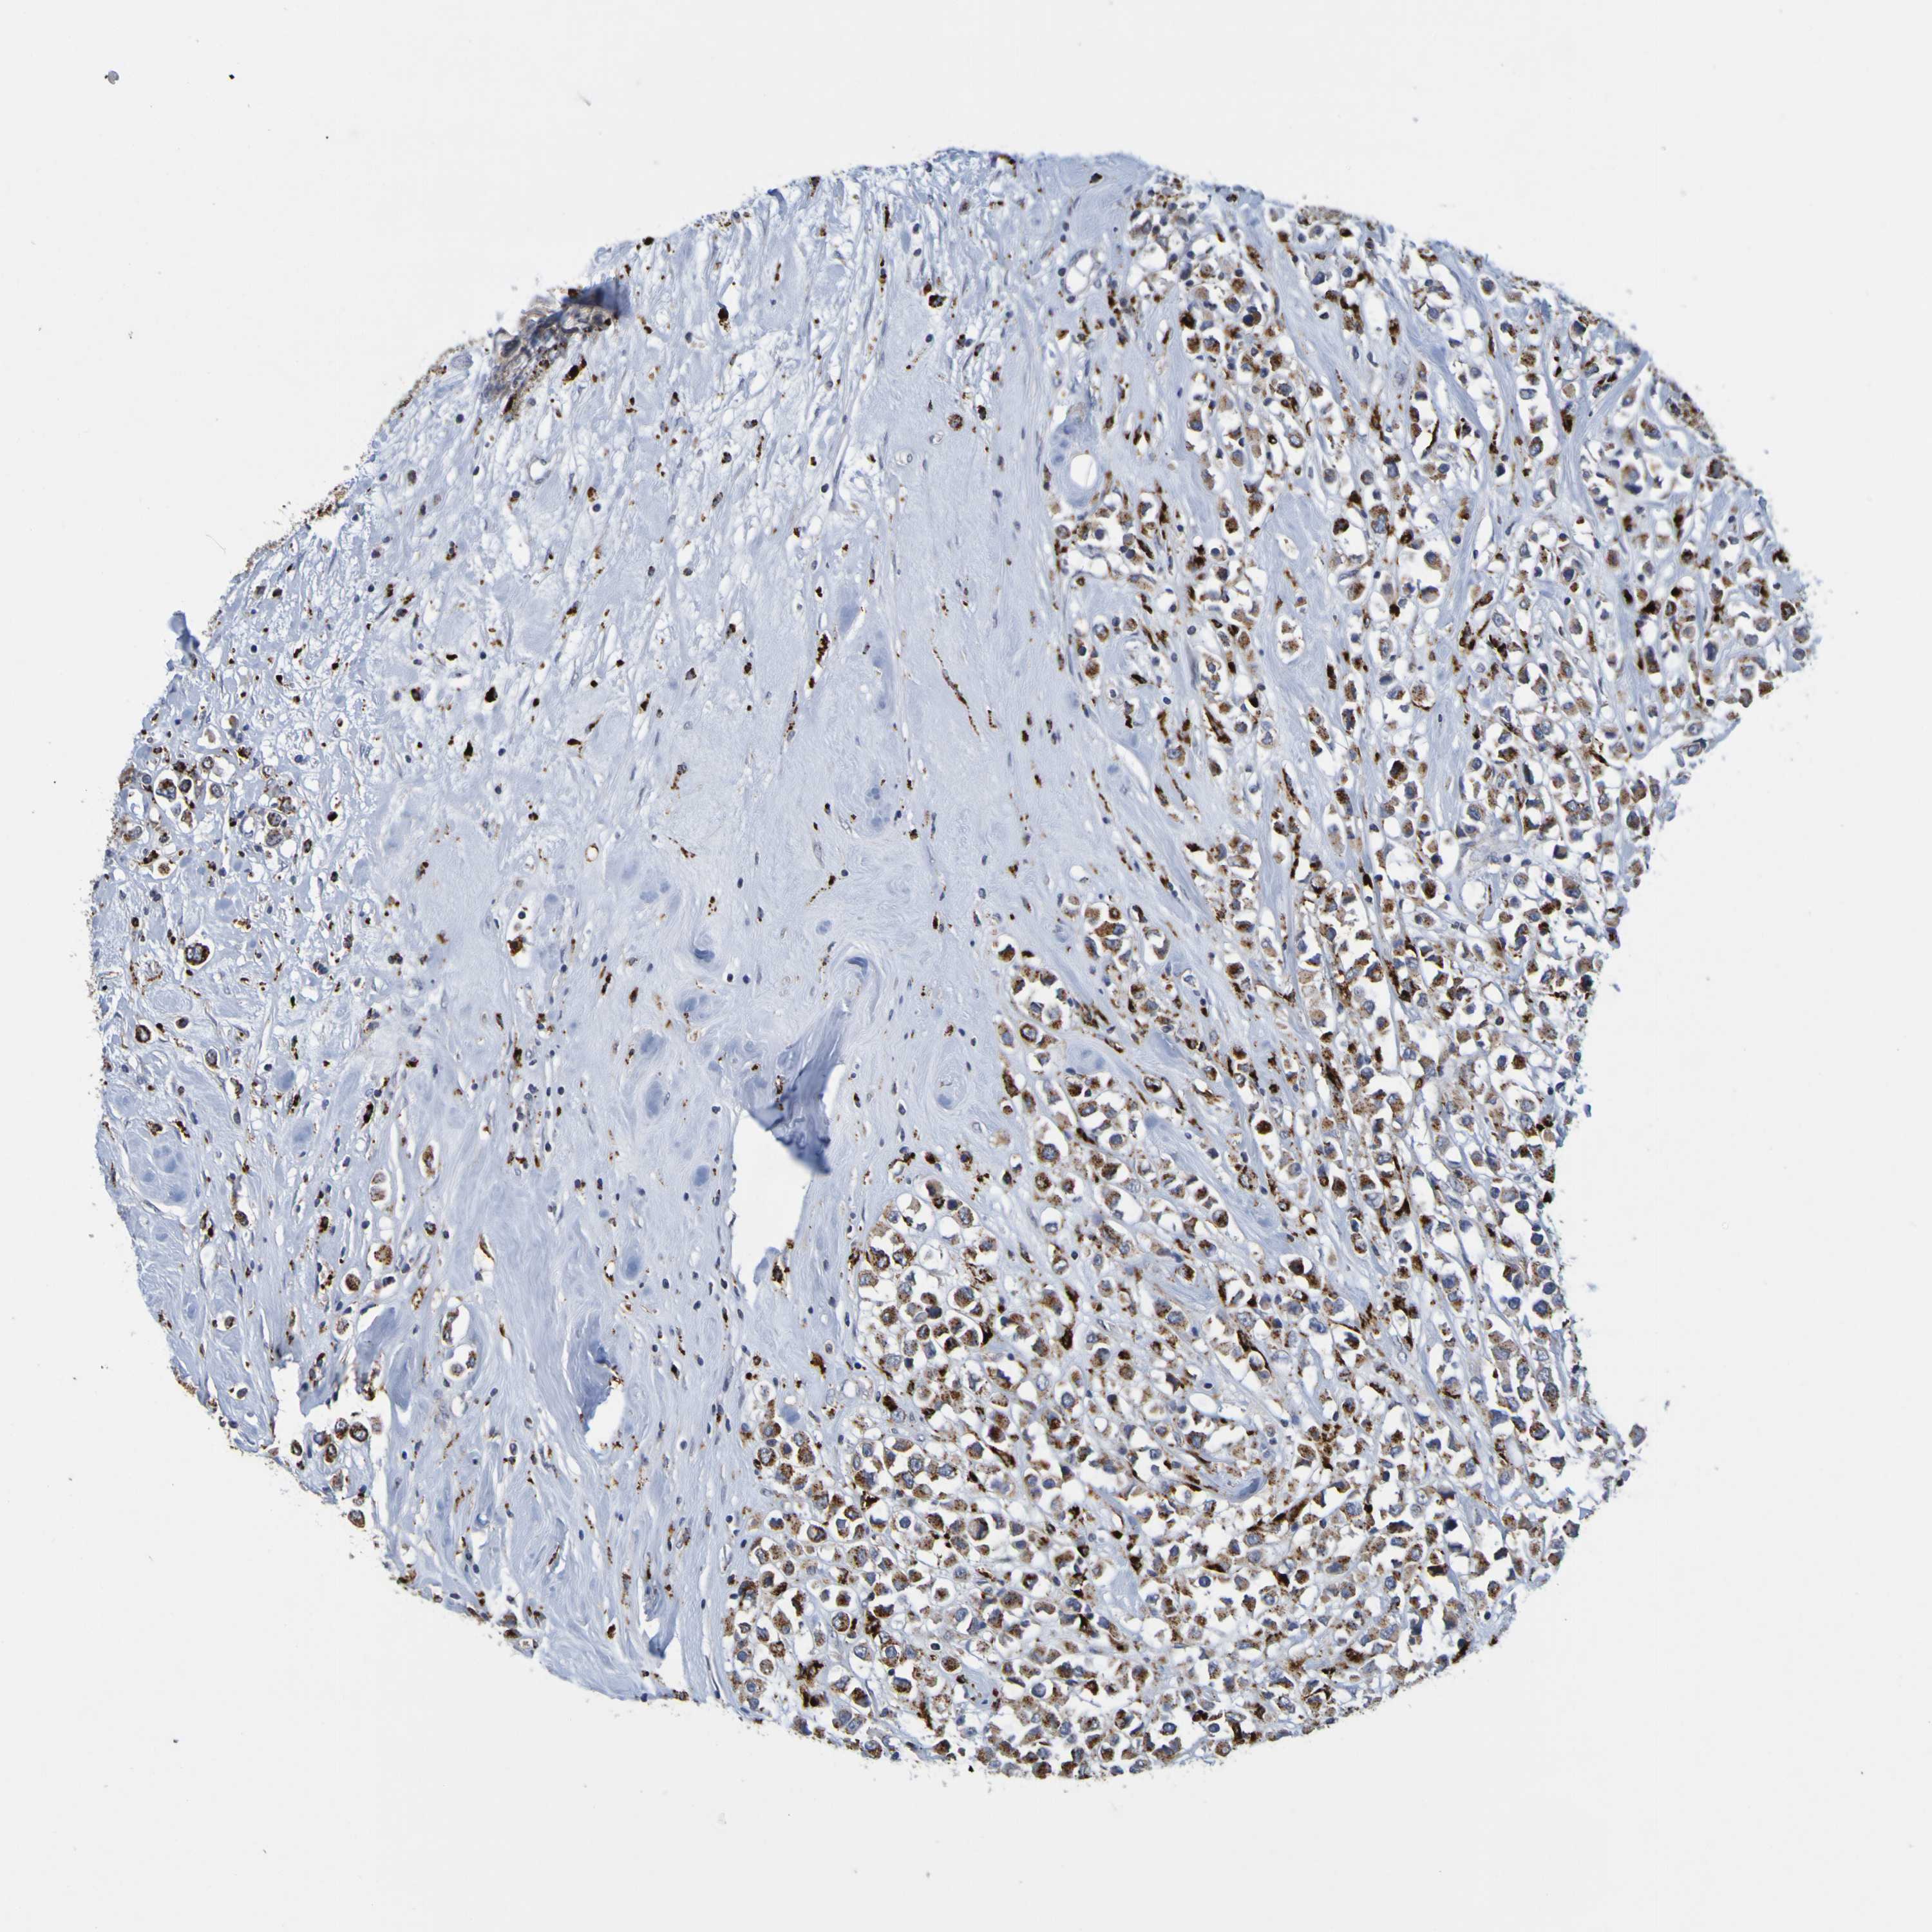

CANCER BREAST CANCER Show tissue menu

BRCA TCGA BRCA VALIDATION PROTEIN EXPRESSION